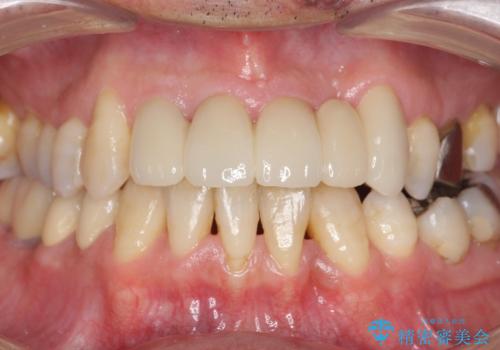

総合歯科治療 → インプラント&根管治療&矯正歯科